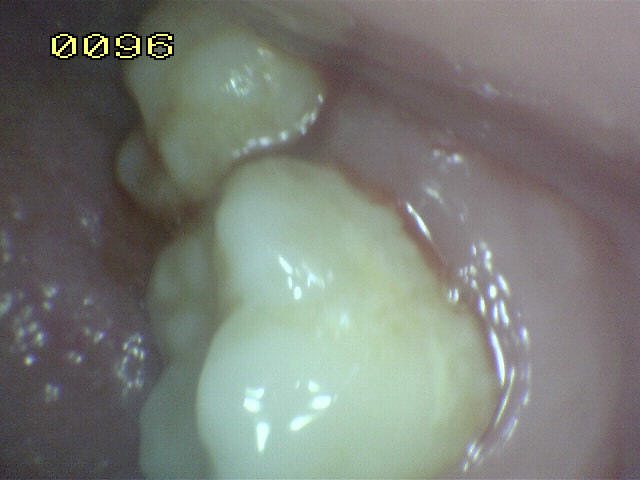

Encía inflamada |

Encía levemente inflamada con un

componente fibroso. Observe el borde gingival con aspecto

liso, turgente y brillante de color rojo |